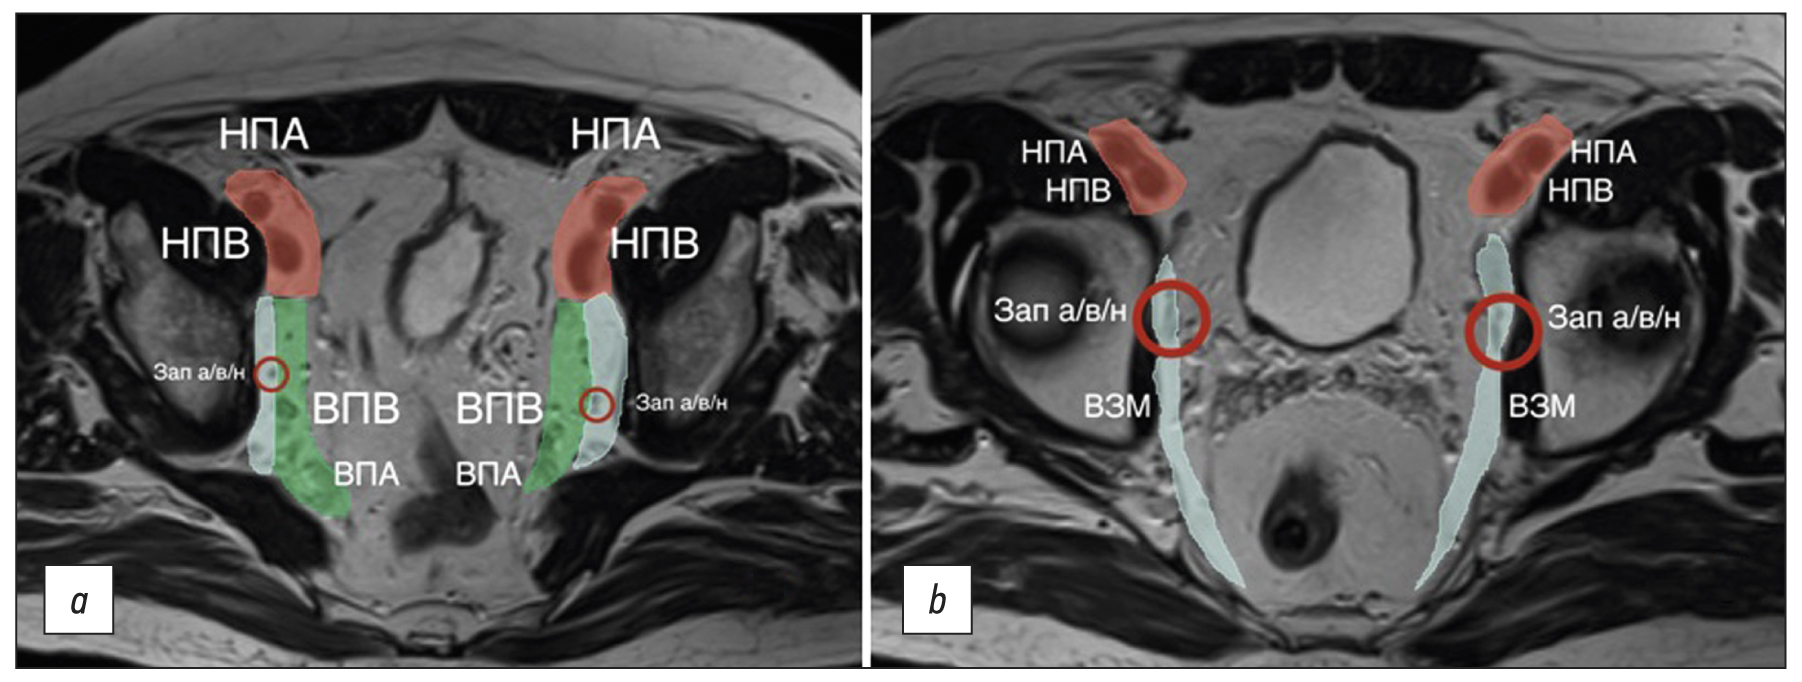

Not all lymph nodes located in the pelvis are regional for rectal cancer and are classified as “N.” When assessing pelvic lymph nodes as regional, it is important to consider their location (Fig. 4) and, if possible, indicate it in the examination report. Here are terms related to location, staging, and criteria for lymph node involvement.

The internal iliac lymph nodes are regional and, in the case of rectal cancer, are included in the scope of dissection of the lateral pelvic lymph nodes. They are located along the internal iliac vessels. At the level of the obturator muscle, they are localized medially to the internal iliac artery; lymph nodes lateral to the internal iliac artery are considered obturator lymph nodes (Fig. 4).

Fig. 4. Localization of the lateral pelvic lymph nodes (colored): external iliac lymph nodes are red; obturator lymph nodes are blue; and internal iliac lymph nodes are green. Shown in levels (a) proximal and (b) distal. EIA: external iliac artery; EIV: external iliac vein; IIV: internal iliac vein; IIA: internal iliac artery; Obt a/v/n: obturator artery/vein/nerve; OIM: obturator internus muscle.

The obturator lymph nodes are regional. They are located between the external and internal iliac arteries, medially to the internal obturator muscle and laterally to the internal iliac artery (Fig. 4).

The external iliac lymph nodes are not regional. They are located along the external iliac vessels (Fig. 4) and are divided into lateral, middle/median, and medial chains. The lateral subgroup is located laterally to the external iliac artery. The middle/median group is between the artery and the vein. The medial group is posterior to the external iliac vein. The lymph nodes in the medial subgroup are located near the obturator vessels and obturator lymph nodes. This can cause diagnostic difficulties because they are often indistinguishable from the obturator lymph nodes localized along the obturator artery at the point of its origin from the internal iliac (hypogastric) artery at the level of the internal obturator muscles [3]. Involvement of the external iliac lymph nodes in rectal cancer is extremely rare. Non-regional lymph nodes are considered suspicious if they measure >10 mm in short axis.